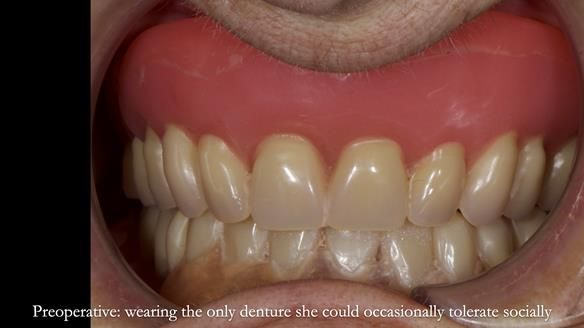

Welcome to Newsletter 83. This month I am sharing Sheila’s case — a very challenging but rewarding complete denture case. Sheila had flat ridges, a small mouth opening, a large tongue and had never been able to wear complete dentures of any kind. Everything was loose and sore. She felt embarrassed and looked older without dentures. She wanted a stable, comfortable result, and she wanted to avoid implants because she has taken bisphosphonates for more than five years.